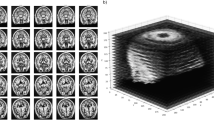

(a) Segmentation results of CNN-based V-Net (left 3D images in first column and red-highlighted areas in second column) and FS (right 3D images in first column and blue-highlighted areas in second column) for each brain structure. (b) Segmentation results of ViT-based UNETR (left 3D images in first column and red-highlighted areas in second column) and FS (right 3D images in first column and blue-highlighted areas in second column) for each brain structure.

Segmentation and prediction results of V-Net, UNETR and FS are illustrated in Fig. 2. The Dice score was obtained (Supplementary Table S1) to evaluate the performance of 3D image segmentation. The CNN- and ViT-based models showed high Dice scores above 0.85 for all the brain structures. The Dice scores were higher for the midbrain and pons than for the basal ganglia (i.e., caudate, putamen, pallidum), possibly because the brainstems are surrounded by cerebrospinal fluid and provide a stronger contrast for accurate segmentation. The ViT-based model showed a higher Dice score than the CNN-based model, which in turn showed a much shorter segmentation time than the ViT-based model (e.g., 51.26 s for V-Net and 1101.82 s for UNETR, as shown in Table 1). Although we evaluated V-Net and UNETR in different development environments of TensorFlow and PyTorch, respectively, we expect the CNN-based V-Net to be competitive in speed with the ViT-based UNETR given the segmentation speed difference of at least 10 times in our experiments. In addition, the CNN-based V-Net had a similar performance to the ViT-based UNETR in actual disease classification, as listed in Table 2.

In this study, the final segmentation result was assessed with the same input size of \(256 \times 256 \times 128\). The original size of the segmentation result was \(256 \times 256 \times 256\), but it was adjusted to \(256 \times 256 \times 128\) for comparison with the DL models. In addition, we replaced FS with a DL model applied to the skull-stripped MRI scan (i.e., pre-processing result of the recon-all pipeline) to perform segmentation. For the replacement, we evaluated whether the DL analysis is faster than FS analysis and whether the segmentation result of DL is sufficiently reproducible compared with that of FS. The differences between FS and DL segmentation are illustrated in Fig. 2.